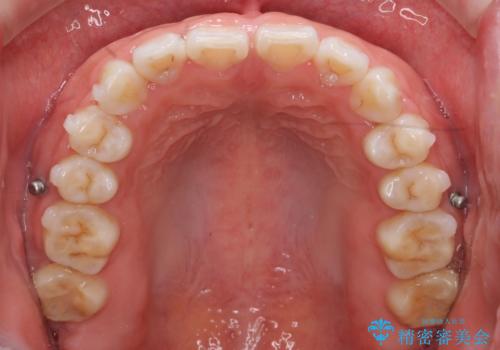

インビザライン 気になるすきっ歯の改善

- 上下顎前歯部の空隙が気になるので治したいと当院にいらっしゃった方の症例です。

非抜歯、インビザラインによる矯正治療により歯と歯の隙間および前歯の上下の隙間を閉じ切りました。

プレートタイプの保定装置について

当院では日中に使っていただく審美性に優れたマウスピースタイプの保定装置とは別に、プレートタイプの保定装置をお作りするすることもできます。

プレートタイプの保定装置は清掃性が高く、臼歯離開(上下の奥歯どうしに隙間ができる症状)等、咬み合わせの問題が生じにくいのが特徴です。